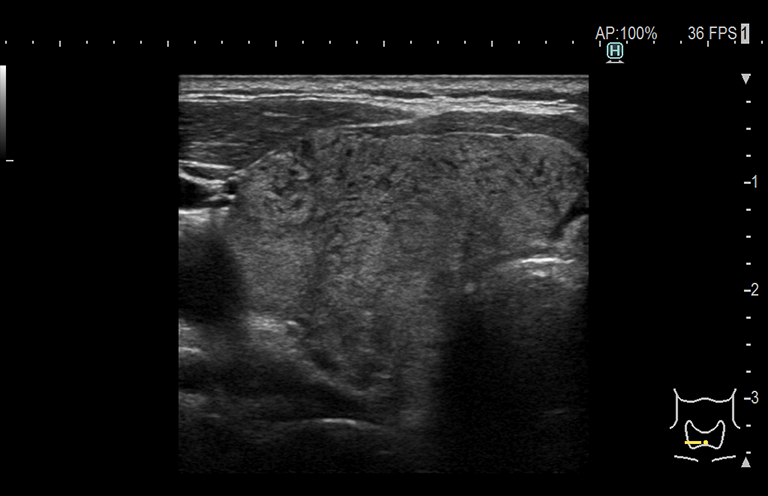

Aplicación: Mama

Función/análisis: Modo B

Comentarios: Mama